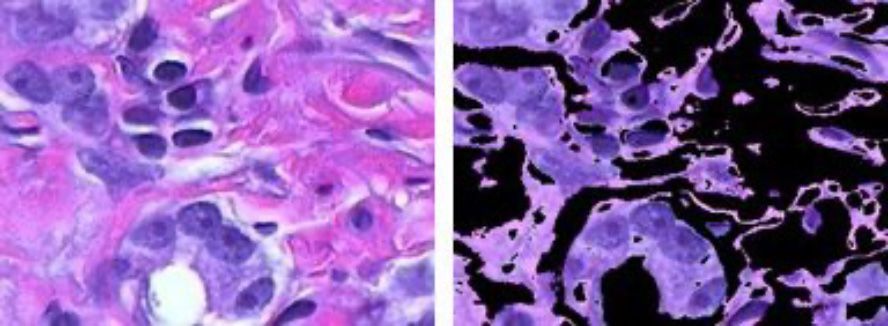

Segmentación de imágenes basada en color con clusters de K-means.